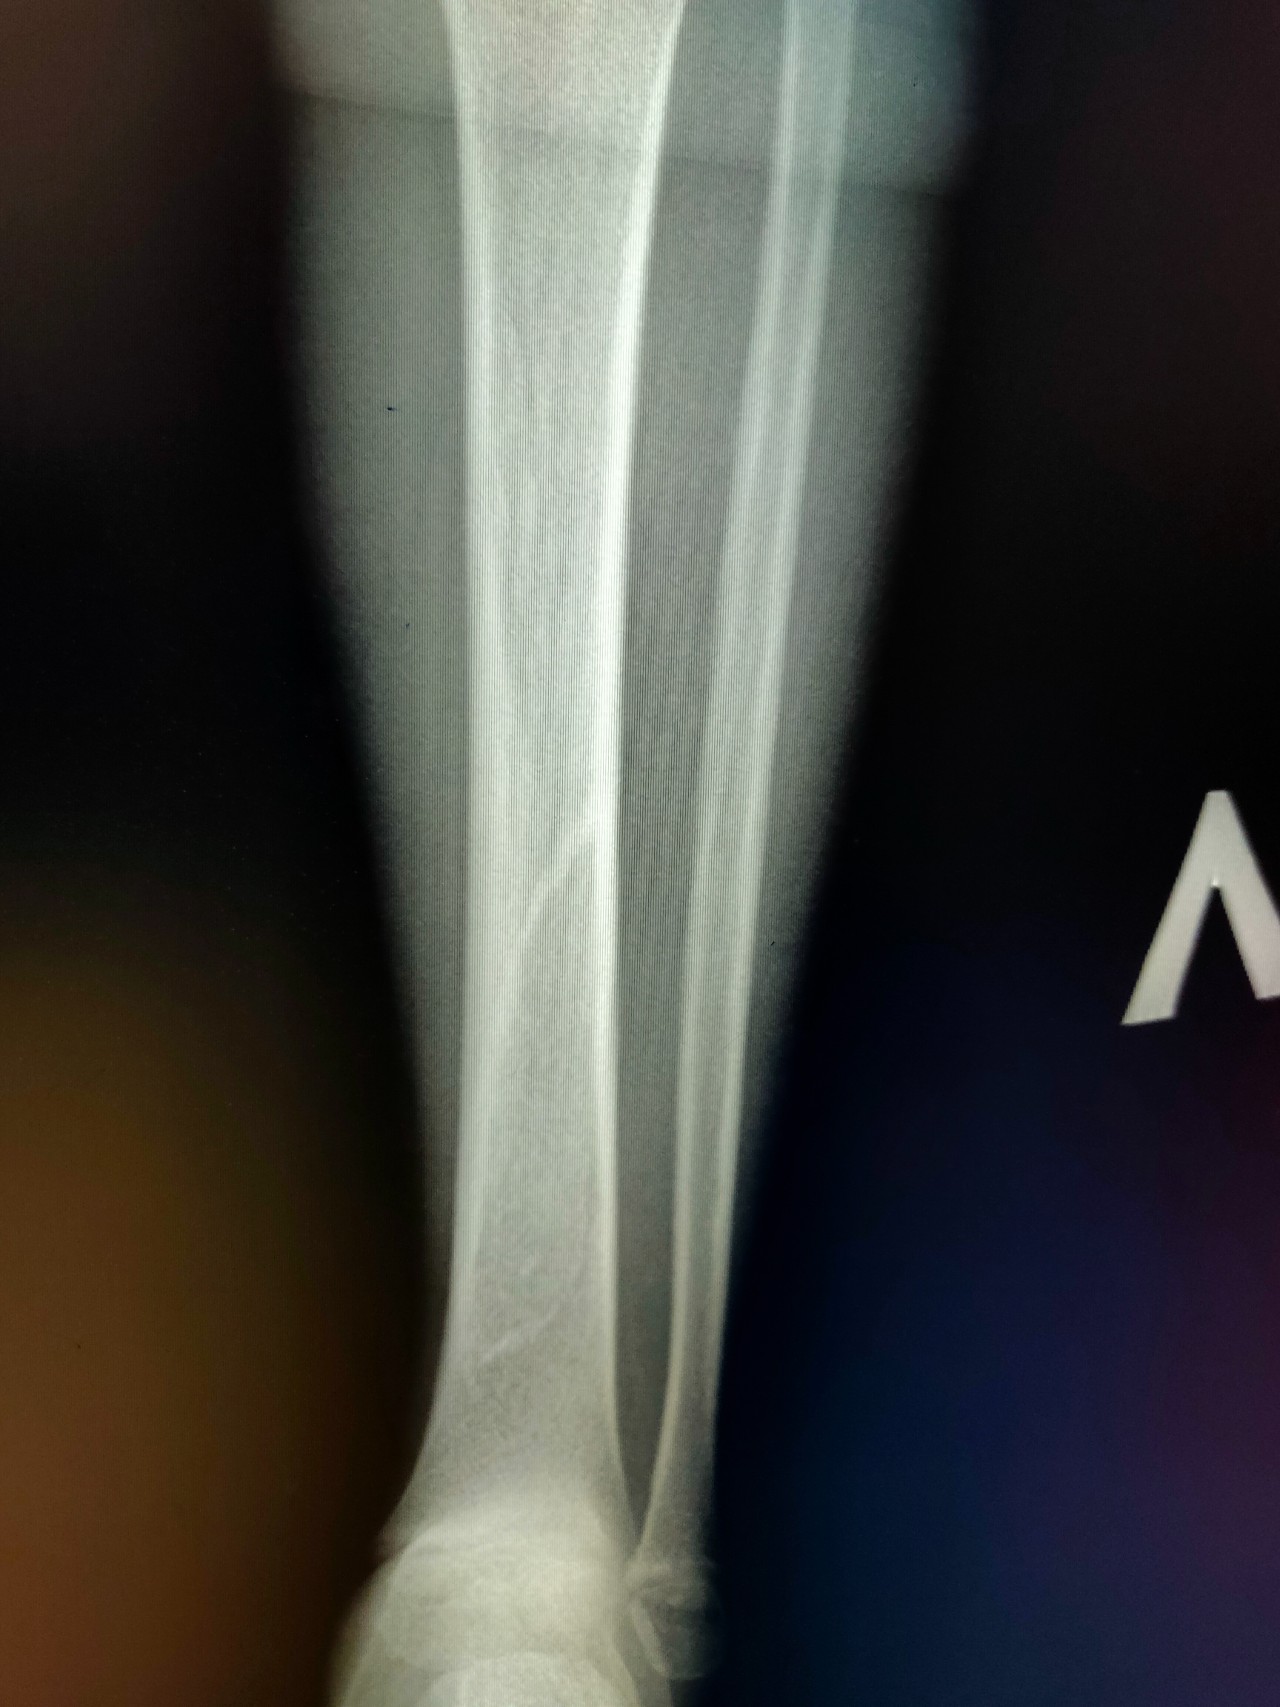

Перелом большой берцовой кости - серьезное повреждение, сопровождающееся болезненными ощущениями и нарушением функции ноги. На этой странице вы найдете много фотографий, позволяющих вам более детально изучить эту травму.

Большеберцовая кость рентген

Здесь представлены медицинские изображения переломов большой берцовой кости, сделанные врачами в процессе диагностики и лечения. Вы сможете увидеть, как выглядит этот тип травмы на рентгеновских снимках и других медицинских изображениях.